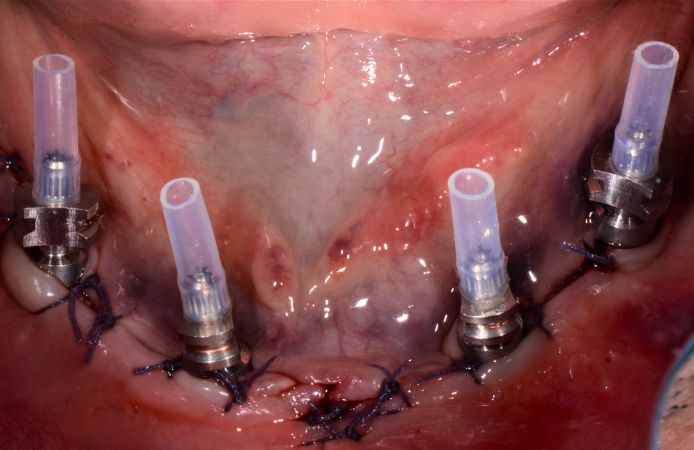

- Immediate placement of four implants with Multi-Unit Abutments.

- Provisional screw-retained bridge placement during the preparation of the final prosthesis.

Figure 3.